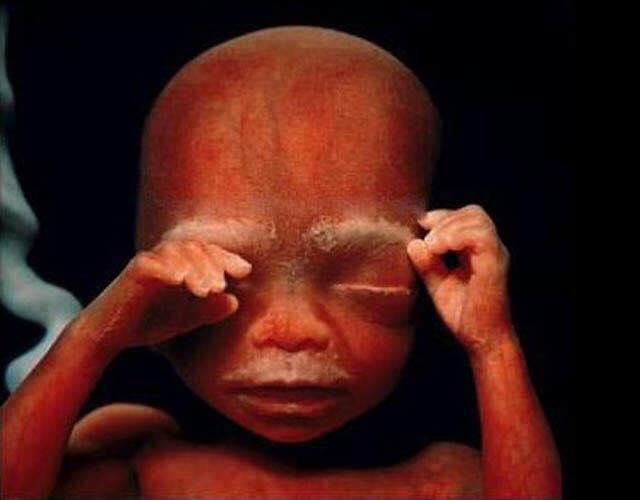

Semana 16, medindo por volta de 11,5 centímetros e pesando aproximadamente 100 gramas

O esqueleto consiste basicamente em cartilagem e o sistema circulatório é visível através da pele translúcida